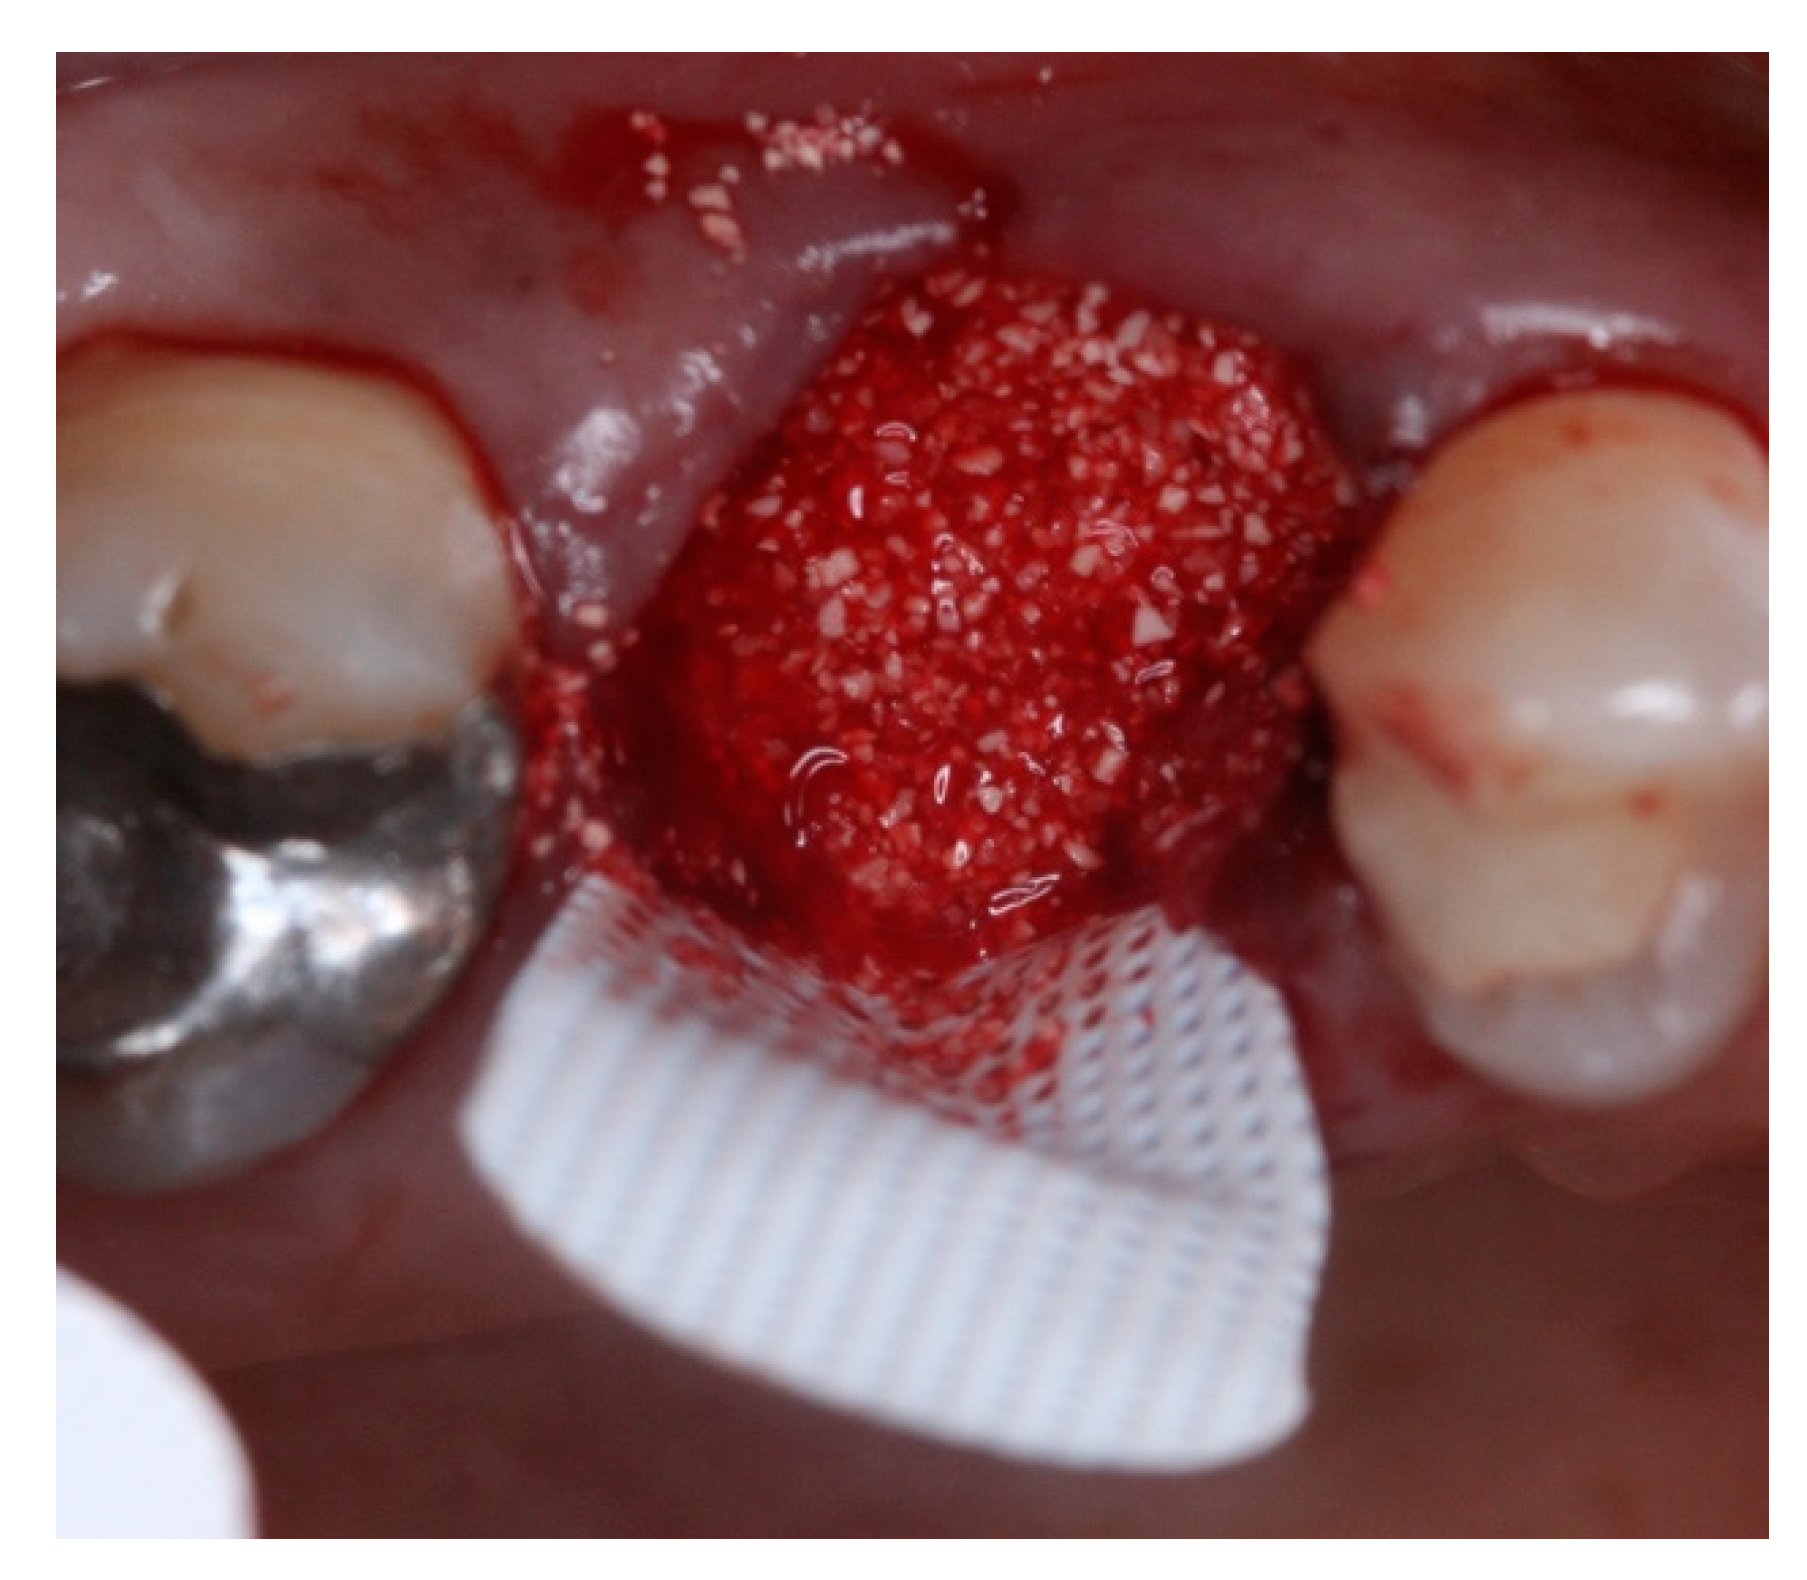

2. Materials and Methods